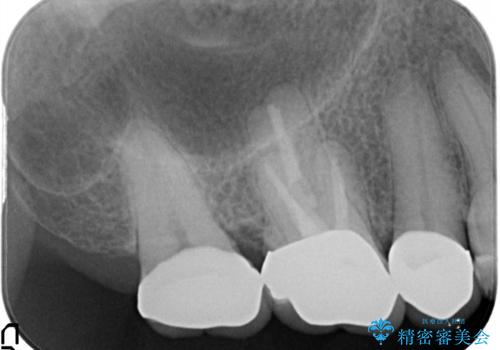

- 右上の奥歯がしみるとのことで確認すると、右上の一番奥の歯の銀歯の下が虫歯になっていました。

かなり大きな銀歯が装着されていたので、かぶせ物にて治療を行うこととなりました。

同時に右上の後ろから3番目の歯のかぶせ物も適合が悪かったので同時に治療することとなりました。

虫歯もしっかり除去して、適合の良い補綴物を装着しました。